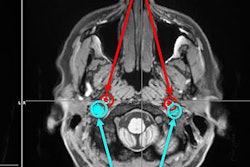

The figure shows two different brains aligned to a common template space for comparison. The yellow in the anterolateral entorhinal cortex of the young brain indicates significant activity, something that is absent in the older brain. Courtesy of Zachariah Reagh, PhD.Reagh and colleagues now plan to explore whether this type of fMRI scan could eventually be used as a tool for early diagnosis. They will expand their work to a sample of 150 older adults who will be followed over time, and the subjects will also receive PET scans to track amyloid and tau pathology.